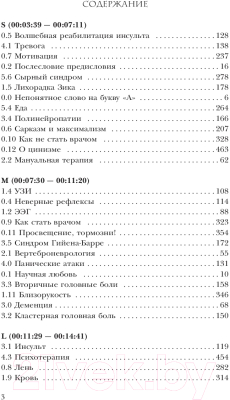

Книга АСТ, Модицина 2. Апология

| Автор: | Жуков Н. |

| Категория: | научно-популярная литература |

| Тематика: | медицина |